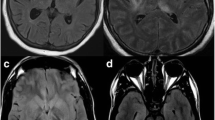

Acute necrotizing encephalopathy is less frequent than ADEM. ANE is a distinct form of acute encephalopathy triggered by respiratory tract infections, especially viral infections such as influenza A and B [32]. First described as a novel disease by Mizuyuchi in 1995, the condition has been reported mainly from Japan, although increasingly ANE is recognized in multiple countries [33]. It is not a rare encounter among pediatric infectious diseases subspecialists in the United States. Affected children usually are 5 months to 10 years of age, previously healthy, who in the peak of a febrile respiratory tract illness have acute onset of seizures or changes in mental status or both; global suppression ranges from obtundation to coma. Specific neurologic abnormalities are not universal, but speech abnormalities and akinetic mutism as well as delirious behavior [34] may occur more commonly in ANE than in acute infectious encephalitis or ADEM. CSF is acellular, glucose concentration is normal, and protein concentration typically is normal or mildly elevated. Serum hepatic enzymes may be elevated, severity of which has been associated with poor prognosis in Japanese children. The hallmark of ANE is the MRI findings on T2-weighted images of high intensity signal diffusely and symmetrically in the periventricular white matter – characteristically affecting the thalamus, internal capsule, cerebellum, and brainstem in some cases. Changes are seen within 12 h after onset of coma.

Neuroimaging, especially MRI, has added immeasurably to management and to diagnostic approach in patients with encephalitis syndromes. Specificity of MRI for diagnosis is beyond the scope of this paper. Basic categorization of findings is useful: normal, predominant gray vs. white matter lesion(s), edema/hydrocephalus, focal vs. multifocal site, symmetric vs. asymmetric distribution, or specific abnormality, such as mass, abscess, calcification, ring lesion, hemorrhage, or meningeal enhancement. Empiric therapy is not limited because of MRI findings but certain findings trigger additional investigations or therapies. A few examples are edema/hydrocephalus for bacteria and fungi; asymmetric white matter abnormalities for ADEM; bilateral, symmetrical increased T2-weighted signal in perivascular deep white matter for ANE; and ring lesions for parasitosis. In patients with normal MRI at presentation whose condition deteriorates or whose diagnosis is unclear, repeated MRI can enlighten next steps in diagnosis and management. Electroencephalopathy, likewise, can show specific abnormalities such as sometimes can be seen in HSV encephalitis or subacute sclerosing panencephalitis or can confirm subclinical seizures, but mostly commonly is nonspecifically abnormal in acute encephalitis of multiple etiologies.